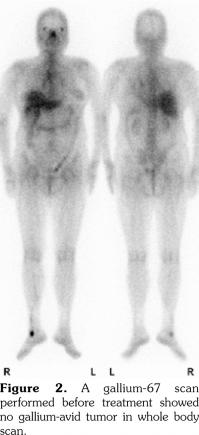

A 53-year-old female patient suffered from pain over most of her body, particularly the joints and the throat. In addition, skin rashes on the trunk without pruritus were noted. She had visited the Rheumatology, Neurology, and Orthopedic Outpatient Department several times. A chest computed tomography (CT) was performed which revealed multiple lymphadenopathies over cervical, mediastinal, and axillary areas. A positron emission tomography (PET)/CT revealed increased fluorine-18-deoxyglucose (FDG) uptake in many lymph nodes including the bilateral neck, axillae, mediastinum, bilateral pulmonary hili, abdominal paraaortic region, iliac regions, and inguinal regions as well as the bone marrow and the spleen (Figure 1). In addition, mild and diffuse increase of FDG uptake in the bone marrow was noted. Lymphoma was suspected first. After discussing with the patient, thoracoscopic mediastinal lymph node biopsy was performed. Fifteen lymph nodes were taken and the results showed histiocytic infiltration in sinusoid area and anthracotic pigment deposition. Reactive lymphoid follicle hyperplasia and focal fibrocalcified nodule formation were also noted. No tumor cell was seen. Gallium-67 (Ga-67) scan was conducted and no gallium-avid tumor was seen throughout the whole body (Figure 2). The laboratory data were negative for antinuclear antibodies, rheumatoid factor- immunoglobulin M, and extractable nuclear antibody, while alanine aminotransferase was high. The final diagnosis was AOSD. In our case, there were no symptoms or signs of either high fever or debilitating joint although the FDG PET showed multiple FDG-avid lesions in the whole body scan. According to the experience of our rheumatologists, methylprednisolone (Metisone) 4 mg/day and non-steroidal anti-inflammatory drugs were prescribed initially and the response to treatment was good. Six months later, the follow- up PET/CT showed complete remission of the FDG-avid lesions seen in the previous PET/CT (Figure 1) and the patient’s symptoms relieved. A written informed consent was obtained from the patient.

In this study, we present the FDG PET/CT and Ga-67 scan findings of a patient who met the Yamaguchi classification criteria for AOSD. The FDG PET/CT scan was not helpful in diagnosing AOSD in this case since lymphoma could not be ruled out. However, the FDG PET/CT scan results were useful for evaluating the distribution and severity of the disease. A negative Ga-67 scan could be beneficial as it would exclude lymphoma. After the diagnosis of AOSD was established, the patient received nonsteroidal anti-inflammatory drugs and glucocorticoids with a good response. Disease activity and therapeutic response were monitored by FDG PET/CT and the findings of a scan performed six months after treatment were negative.(13)